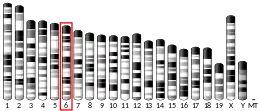

Acquired mutations

The ETV6 gene is prone to develop a wide range of acquired mutations in hematological precursor cells that lead to various types of leukemia and/or lymphoma. It may also suffer a smaller number of mutations in non-hematological tissues that leads to solid tumors. These mutations involve chromosome translocations which fuse the ETV6 on chromosome 12's the short (i.e. "p") arm ("q" stands for long arm) at position p13.2 (site notation: 12p12.2) near to a second gene on another chromosome or, more rarely, its own chromosome. This creates a fusion gene of the oncogene category which encodes a chimeric protein that promotes the malignant growth of its parent cells. It may be unclear which portion of the newly formed oncoprotein contributes to the ensuing malignancy but fusions between ETV6 and proteins with tyrosine kinase activity generally are converted from a protein with tightly regulated tyrosine kinase activity to an uncontrolled and continuously active tyrosine kinase that thereby promotes the malignant transformation of its parent cells.[14]